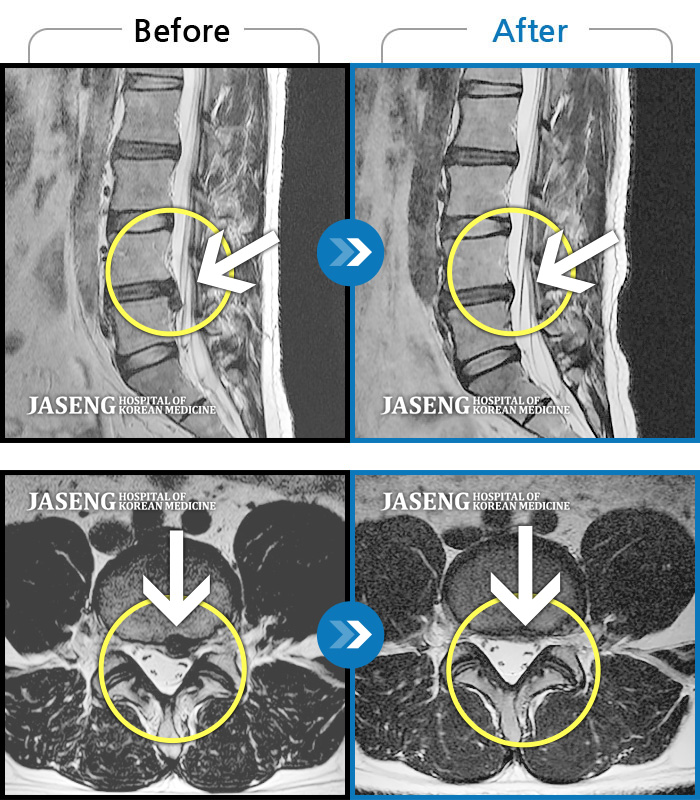

MRI 치료사례